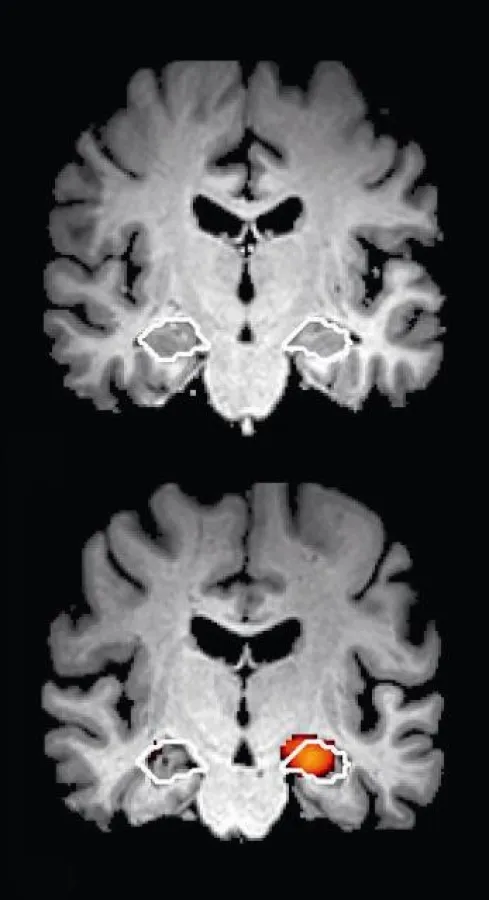

Auch das ist nur die halbe Wahrheit. Die Demenzabklärung beinhaltet zunächst den Einsatz neuropsychologischer Kurztests. Die Dauer dieser Tests beschränkt sich auf wenige Minuten. Mit ihnen lassen sich subjektive Gedächtnisstörungen objektivieren und ein Demenzverdacht begründen. Erst wenn ein Verdacht besteht kommen ergänzende neuropsychologische Tests zum Einsatz. Bei der Alzheimer-Erkrankung kommt es zusätzlich zum Verlust von Nervenzellen in bestimmten Hirnregionen. Ein neues Testverfahren, die Alzheimer-Risikodiagnostik (ARDX), entwickelt von der Firma jung diagnostics aus Hamburg, erlaubt den Nachweis von neuronalen Schädigungen in den Alzheimer-typischen Regionen. Ein positives Testergebnis geht mit einem erhöhten individuellen Alzheimer-Risiko einher. Aus diesem Grund sollte sich eine ergänzende fachärztliche Abklärung anschließen, um ggfs. eine leitliniengerechte Diagnose mit anschließender Therapie einzuleiten. Bei fehlendem Nachweis kann eine Alzheimer-Demenz hingegen als Ursache der Gedächtnisstörungen zuverlässig ausgeschlossen werden. Die ARDX kombiniert den Einsatz etablierter kognitiver Kurztests mit der modernen medizinischen Bildgebung und auf ihr basierenden innovativen computergestützten Analyseverfahren. Die Magnetresonanztomographie (MRT) ist nebenwirkungs- und strahlungsfrei. Die gesamte Untersuchungszeit beträgt weniger als eine Stunde. Die ARDX stellt eine schnelle und bequeme Möglichkeit zur Abklärung des individuellen Alzheimer-Risikos dar.